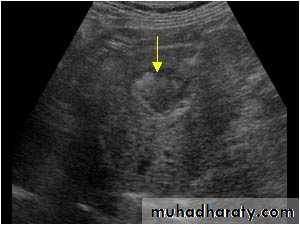

Focal masses ultrasound

Multiple masses